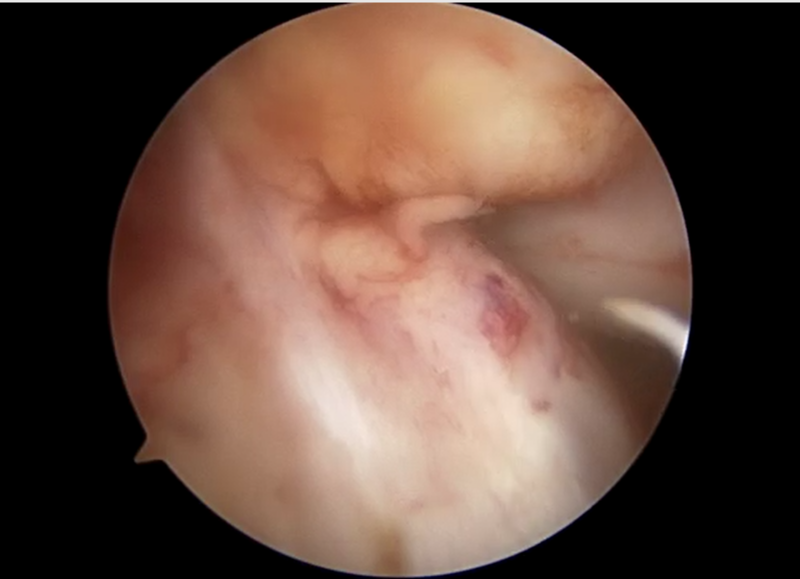

![]() |

| 前十字靭帯損傷部 | 大腿骨側骨孔作成 | 脛骨骨孔作成 |